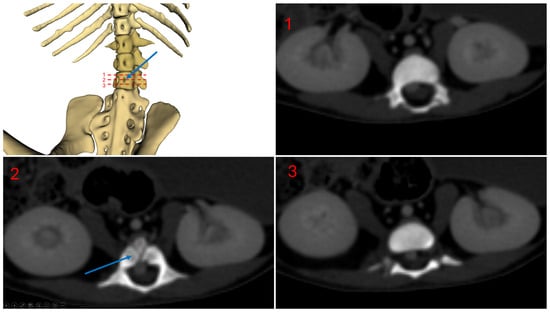

Figure 5 shows a ventral view of subject 1, highlighting the vertebral foramina. The blue arrow indicates the vertebral foramina located on the third lumbar vertebra.

Figure 5.

Subject 1 vertebral foramina, L3 level.

3.1. Subject 1

In the first subject, we observed the presence of a venous network originating from the kidneys, at the level of the 3rd lumbar vertebra, converging at the 23rd thoracic vertebra, and continuing its path cranially up to the 18th thoracic vertebra, to the right side of the spine, before terminating (Figure 2 and Figure 3).

This double caudal vena cava communicated with the intravertebral vein through several basivertebral veins, entering through the vertebral foramina (Figure 4 and Figure 5).

A significant part of the venous flow entered the intravertebral foramen through the second ventral sacral foramen, after receiving the veins from the pelvic limbs (Figure 2, Figure 3, Figure 4 and Figure 5).

This subject did not exhibit any visible communication between the pre-hepatic segment of the caudal double vena cava and the post-hepatic segment of the caudal vena cava draining the supra-hepatic veins (Figure 2 and Figure 3).

After entering the vertebral canal through the first and second ventral sacral foramen and vertebral foramina, the venous flow traveled in the right part of the vertebral canal, to the right of the spinal cord, and then described an anastomotic arch around the ninth right rib, and directly drained into the cranial vena cava, via the arch of the azygos vein (Figure 3)

The right atrium received the post-hepatic segment of the caudal vena cava caudally. Cranially, it received the confluence between the cranial vena cava and the arch of the azygos vein, which itself received the intravertebral vein (Figure 3).